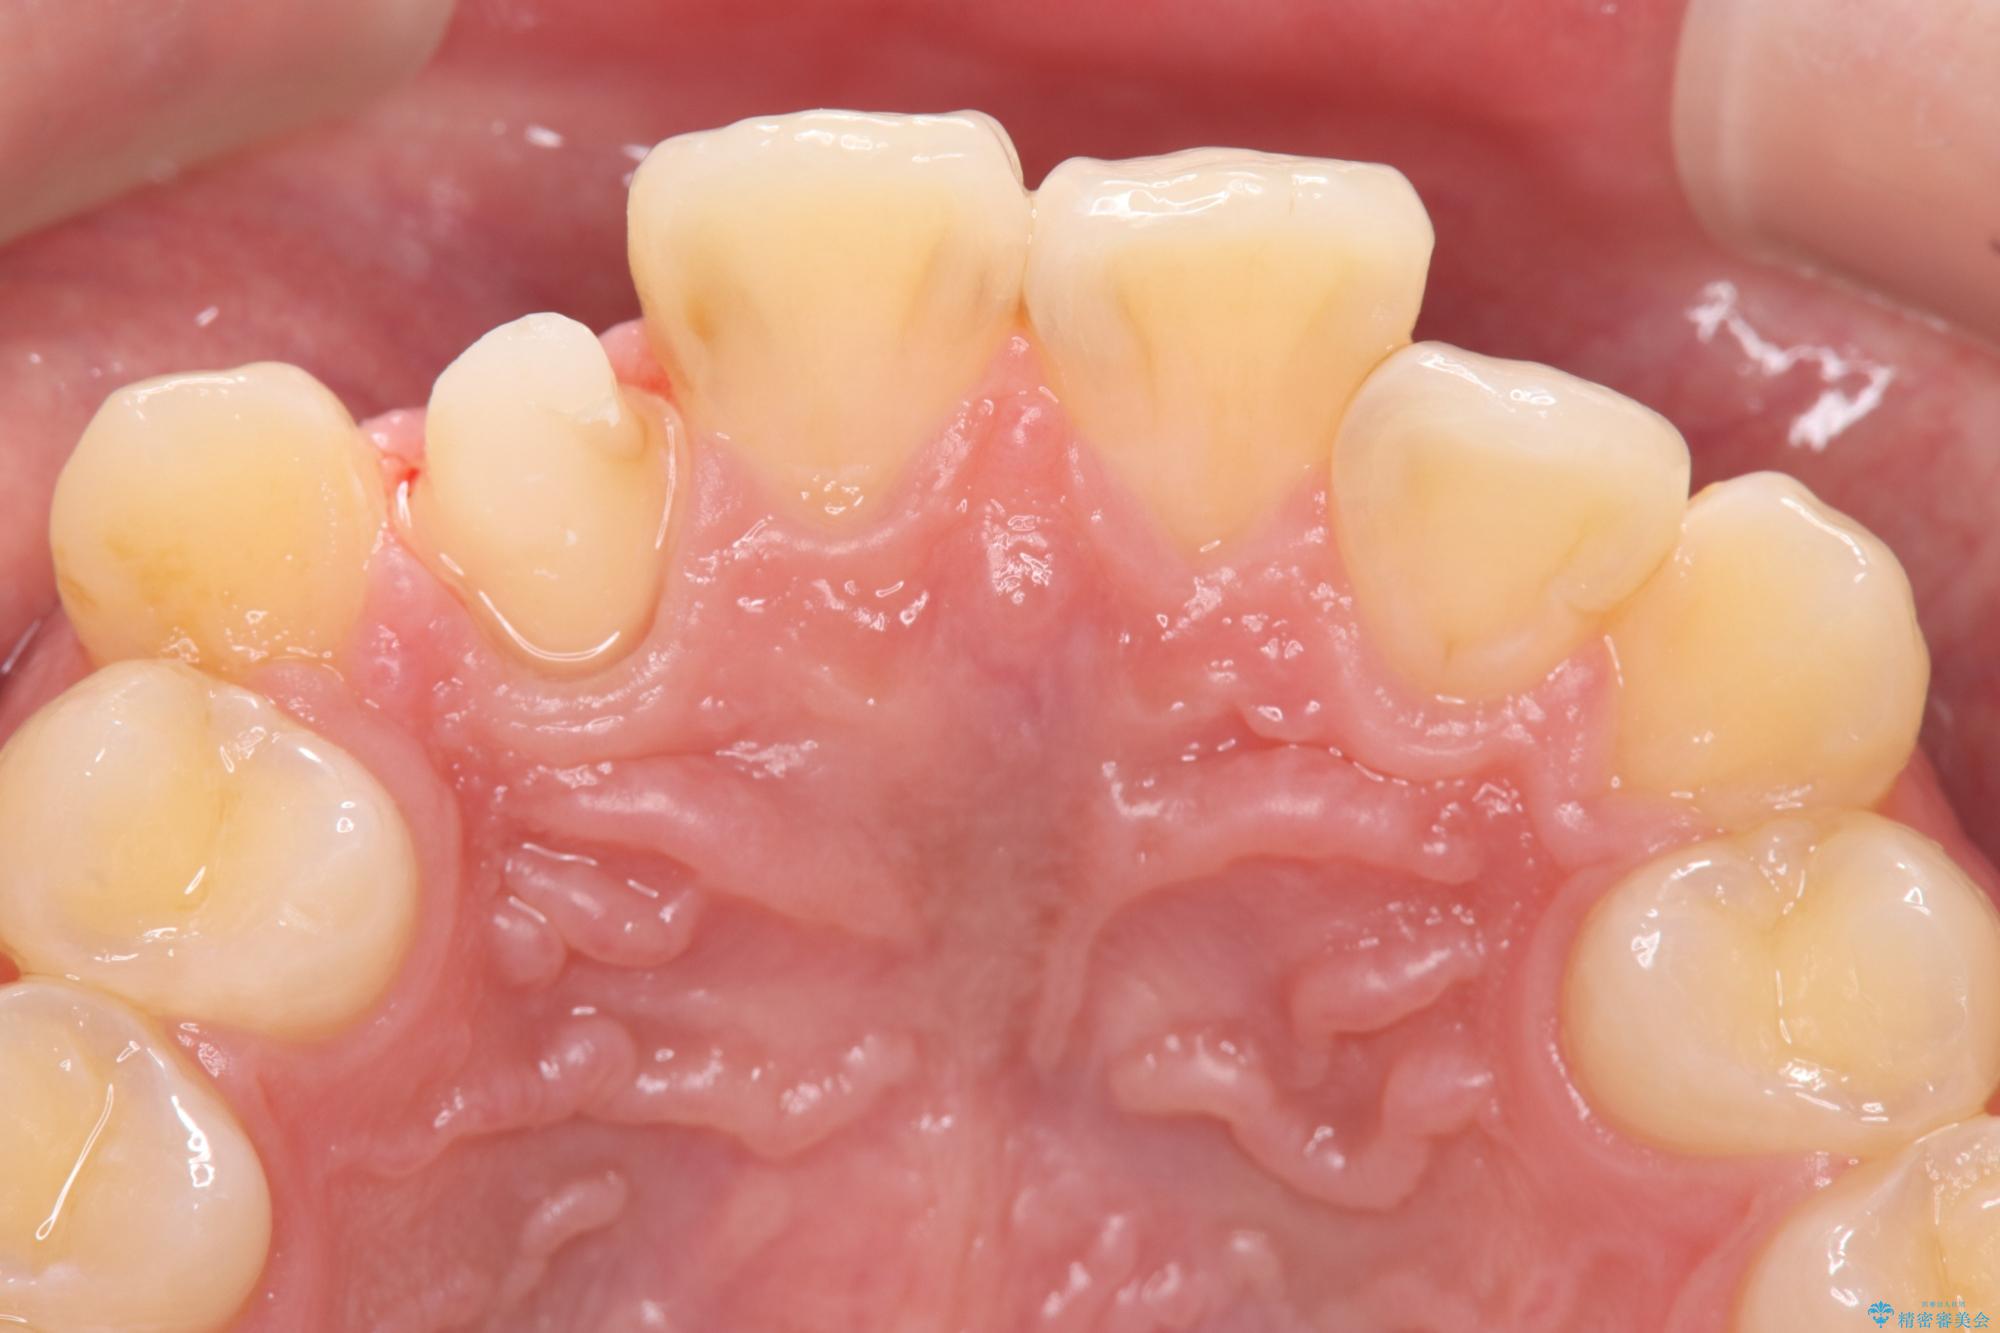

- 主訴:右上の前歯が何しなくても痛い

右上2番の歯に自発痛を認め、症状や歯髄診・レントゲン像から不可逆性歯髄炎と診断し、精密根管治療から歯冠補綴まで行うこととなりました。

初診時に歯髄診断を行い、不可逆性歯髄炎と診断し抜髄から補綴修復までの流れを説明し、精密根管治療、ファイバ-コア築造、オールセラミッククラウン(St)修復を行うこととしました。